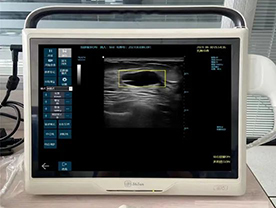

便携式智能彩色超声诊断仪乳腺超声影像智能辅助诊断系统